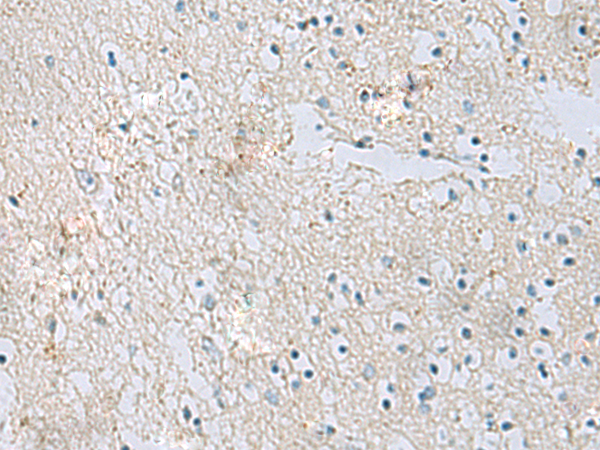

IHC positive control: |

Human brain |

IHC Recommend dilution: |

50-100 |